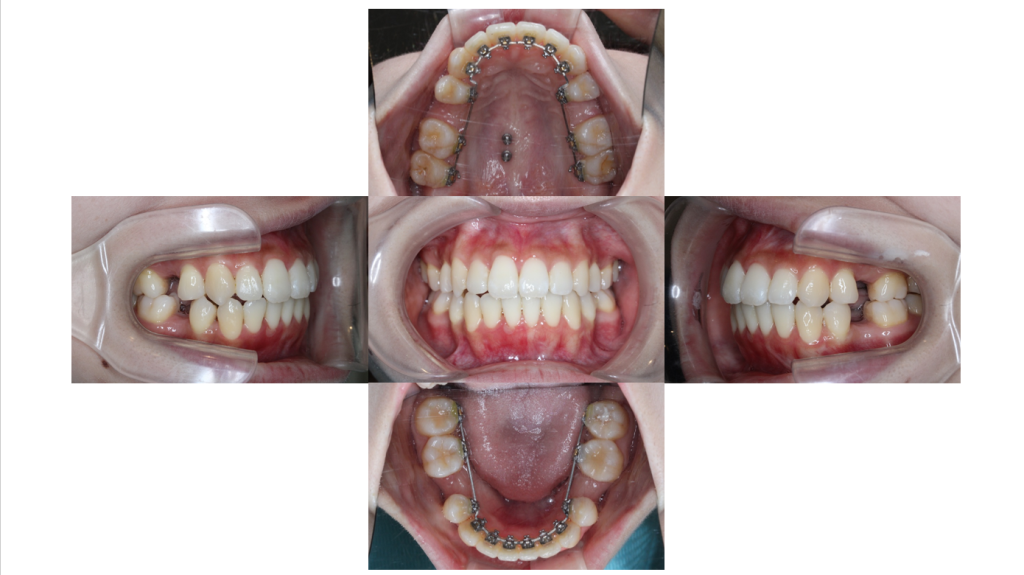

装置装着後

叢生・裏側全体矯正の症例歯に装置を装着しました。

裏側矯正(舌側矯正)で治療をしていきます。